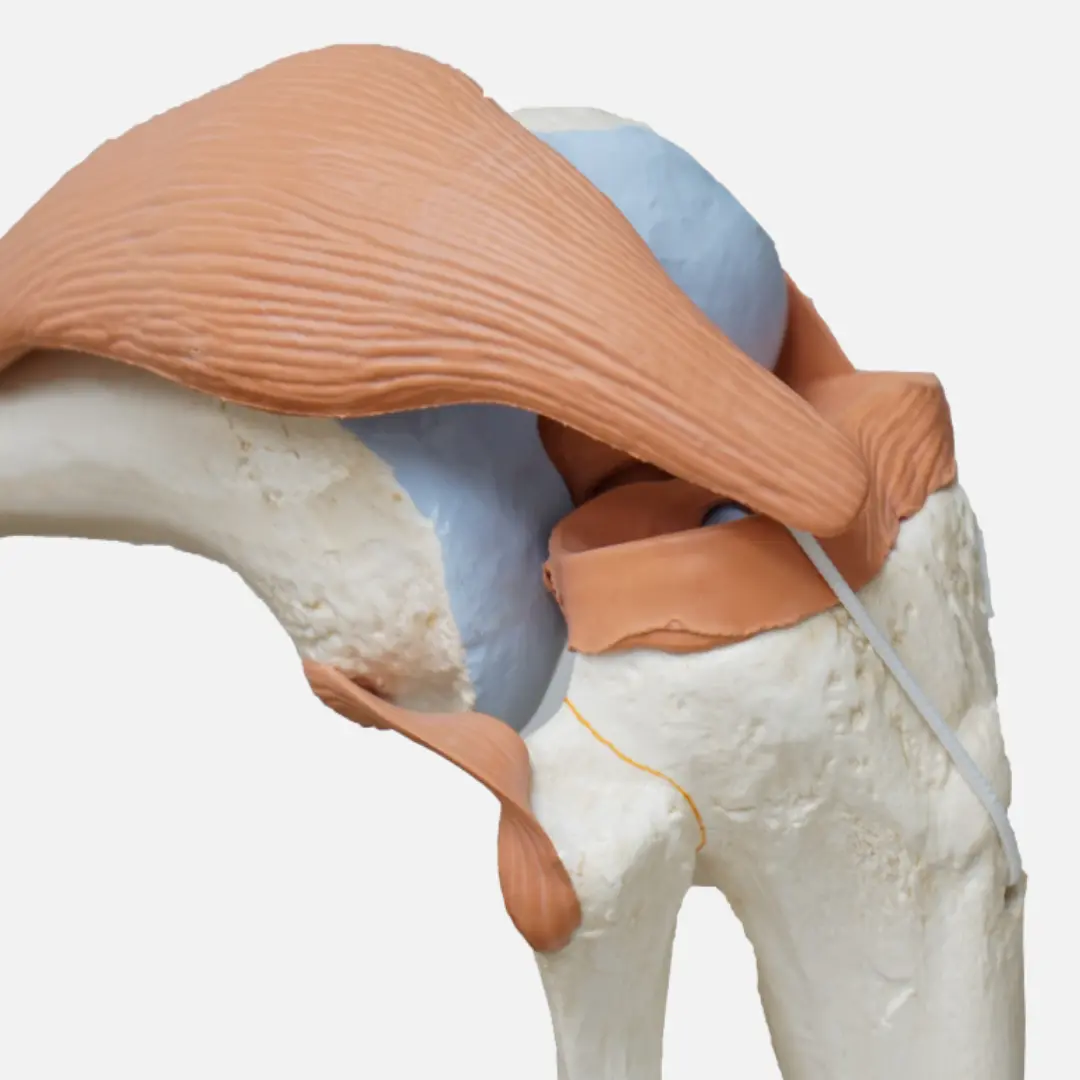

콘드로이친(Chondroitin)은 우리 몸의 연골, 인대, 힘줄, 피부 등 결합 조직에 풍부하게 존재하는 성분입니다. 특히 연골의 주요 구성 성분 중 하나인 프로테오글리칸을 구성하는 핵심 성분이죠. 연골은 관절의 충격을 흡수하고 뼈와 뼈 사이의 마찰을 줄여주는 쿠션 역할을 하는데, 이 연골의 탄력성과 수분 유지를 돕는 것이 바로 콘드로이친입니다.

- 연골이 튼튼해지면 관절의 쿠션 역할이 강화되어 외부 충격을 효과적으로 흡수하고 뼈와 뼈 사이의 마찰을 줄일 수 있습니다.

- 연골 보호, 염증 완화, 수분 유지 등의 복합적인 효능을 통해 전반적인 관절의 유연성과 운동성을 향상시켜 줍니다.